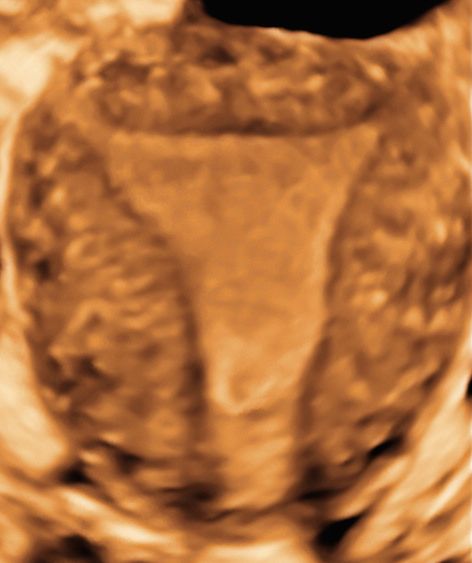

Sono esperta in ecografia 3D (tridimensionale) di cui sono stata docente a livello nazionale ed internazionale per oltre 20 aa, rivestendo incarichi nazionali nell'ambito della Società di Ecografia in Ostetricia e Ginecologia (SIEOG).

ecografia 3D Da 260 €

ecocardiografia fetale Da 260 €